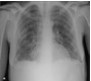

The patient had a high fever, tachycardia, tachypnea, and inspiratory rales in both lung fields but no evidence of hypoxia. White blood cell count was 23,500/μL, with 84% neutrophils. CD4+ cell count was 679/μL (well within the normal range). A chest radiograph revealed bibasilar patchy infiltrate (A).

Therapy with intravenous ceftriaxone and azithromycin was started for presumed community-acquired pneumonia, and the patient was isolated as a precaution. Her clinical condition did not improve with antibiotic and supportive treatment. No acidfast bacilli were isolated from sputum samples. A CT scan of the chest showed extensive bilateral basilar pneumonitis (B). Multiple small cavities in both lungs were also noted. A subsequent bronchoscopy with lavage and bronchial washing isolated Serratia marcescens.